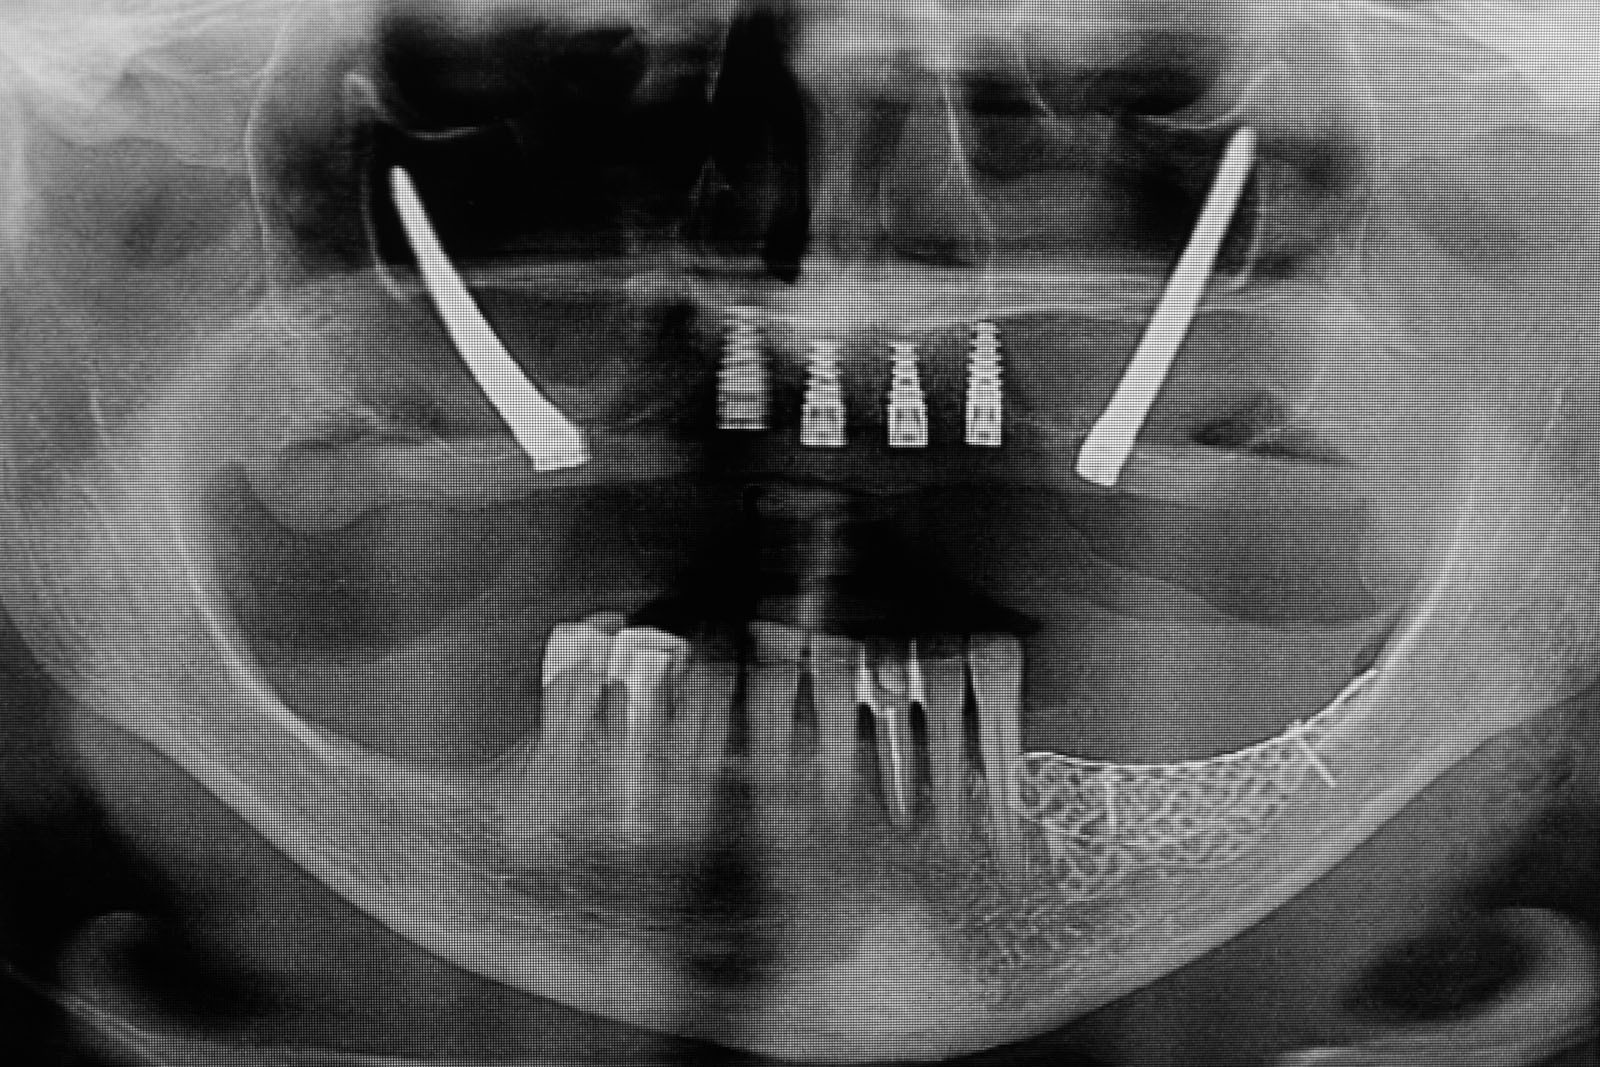

To kolejna metoda umożliwiająca precyzyjną odbudowę zadanego kształtu tkanki kostnej przy użyciu standardowych materiałów kościotwórczych, kości własnej lub PRF oraz zewnętrznego rusztowania w postaci siatki z biozgodnego stopu tytanu. Siatka jest indywidualnie projektowana w technologii CAD CAM i następnie drukowana dla konkretnego przypadku.

Dotychczas stosowane stabilizatory zewnętrzne w formie siatek tytanowych używane do regeneracji kostnej lub w zabiegach odtwórczych w chirurgii szczękowo-twarzowej uwzględniały materiały ręcznie doginane i formowane podczas zabiegu operacyjnego. Zastosowanie technologii CAD CAM dla potrzeb druku materiałów przeznaczonych do indywidualnej rekonstrukcji kostnej znacznie poprawiło precyzję i jakość uzyskiwanych efektów. Wdrożenie biozgodnych stopów tytanu do druku siatek zdecydowanie ograniczyło odsetek powikłań zapalnych.

Siatki stanowią stabilną obudowę – ograniczenie nadające kształt regenerowanej kości przy użyciu upakowanego pod nią materiału. Utrzymują i stabilizują rozdrobniony granulat kościotwórczy, co jest warunkiem prawidłowego procesu gojenia, jednocześnie nadając anatomiczny kształt i zakres odbudowie kostnej sprzed jej zaniku.

Precyzja projektu druku siatki bazuje na dokładności odwzorowania kształtu kości w stożkowej tomografii komputerowej CBCT, co zapewnia ich dobre przyleganie do podłoża kostnego oraz ogranicza powstawanie powikłań w postaci obnażania się siatek.

Precyzja projektu oraz materiał, z którego wykonana jest siatka (biozgodny stop tytanu), powodują, że obnażenie się siatki nie zaburza procesu gojenia i regeneracji kostnej. Wymaga jedynie większej ilości kontroli pozabiegowych oraz wzmaga czujność higieniczną zarówno ze strony lekarza, jak i pacjenta.

Ten rodzaj odbudowy kostnej stosowany jest w sytuacjach złożonych, trójwymiarowych 3D ubytków kości, przy których standardowe metody odbudowy są niewystarczające. Ilość kości, którą możemy uzyskać, stosując tę metodę, to nawet kilka centymetrów sześciennych.

Metoda rekonstrukcji kostnej w oparciu o indywidualnie drukowane siatki z tytanu dla implantacji wszczepów śródkostnych stosowana jest najczęściej jako dwuetapowa. W pierwszym etapie odbudowywana jest kość, natomiast implanty wszczepiane są po okresie 4–6 miesięcy. Na wgojenie implantów oczekujemy od 4 do 6 miesięcy w zależności od miejsca ich lokalizacji. Siatka tytanowa po spełnieniu swojej funkcji rusztowania dla odbudowującej się kości jest następnie usuwana w dniu wszczepienia implantu. Jeżeli kość spełnia odpowiednie warunki, istnieje możliwość zastosowania modyfikacji siatki tytanowej, która umożliwia jednoczesne wprowadzenie implantów wraz z odbudową kostną. Wariant ten skraca czas od pierwszego zabiegu do wykonania gotowych koron protetycznych na wprowadzonych implantach.